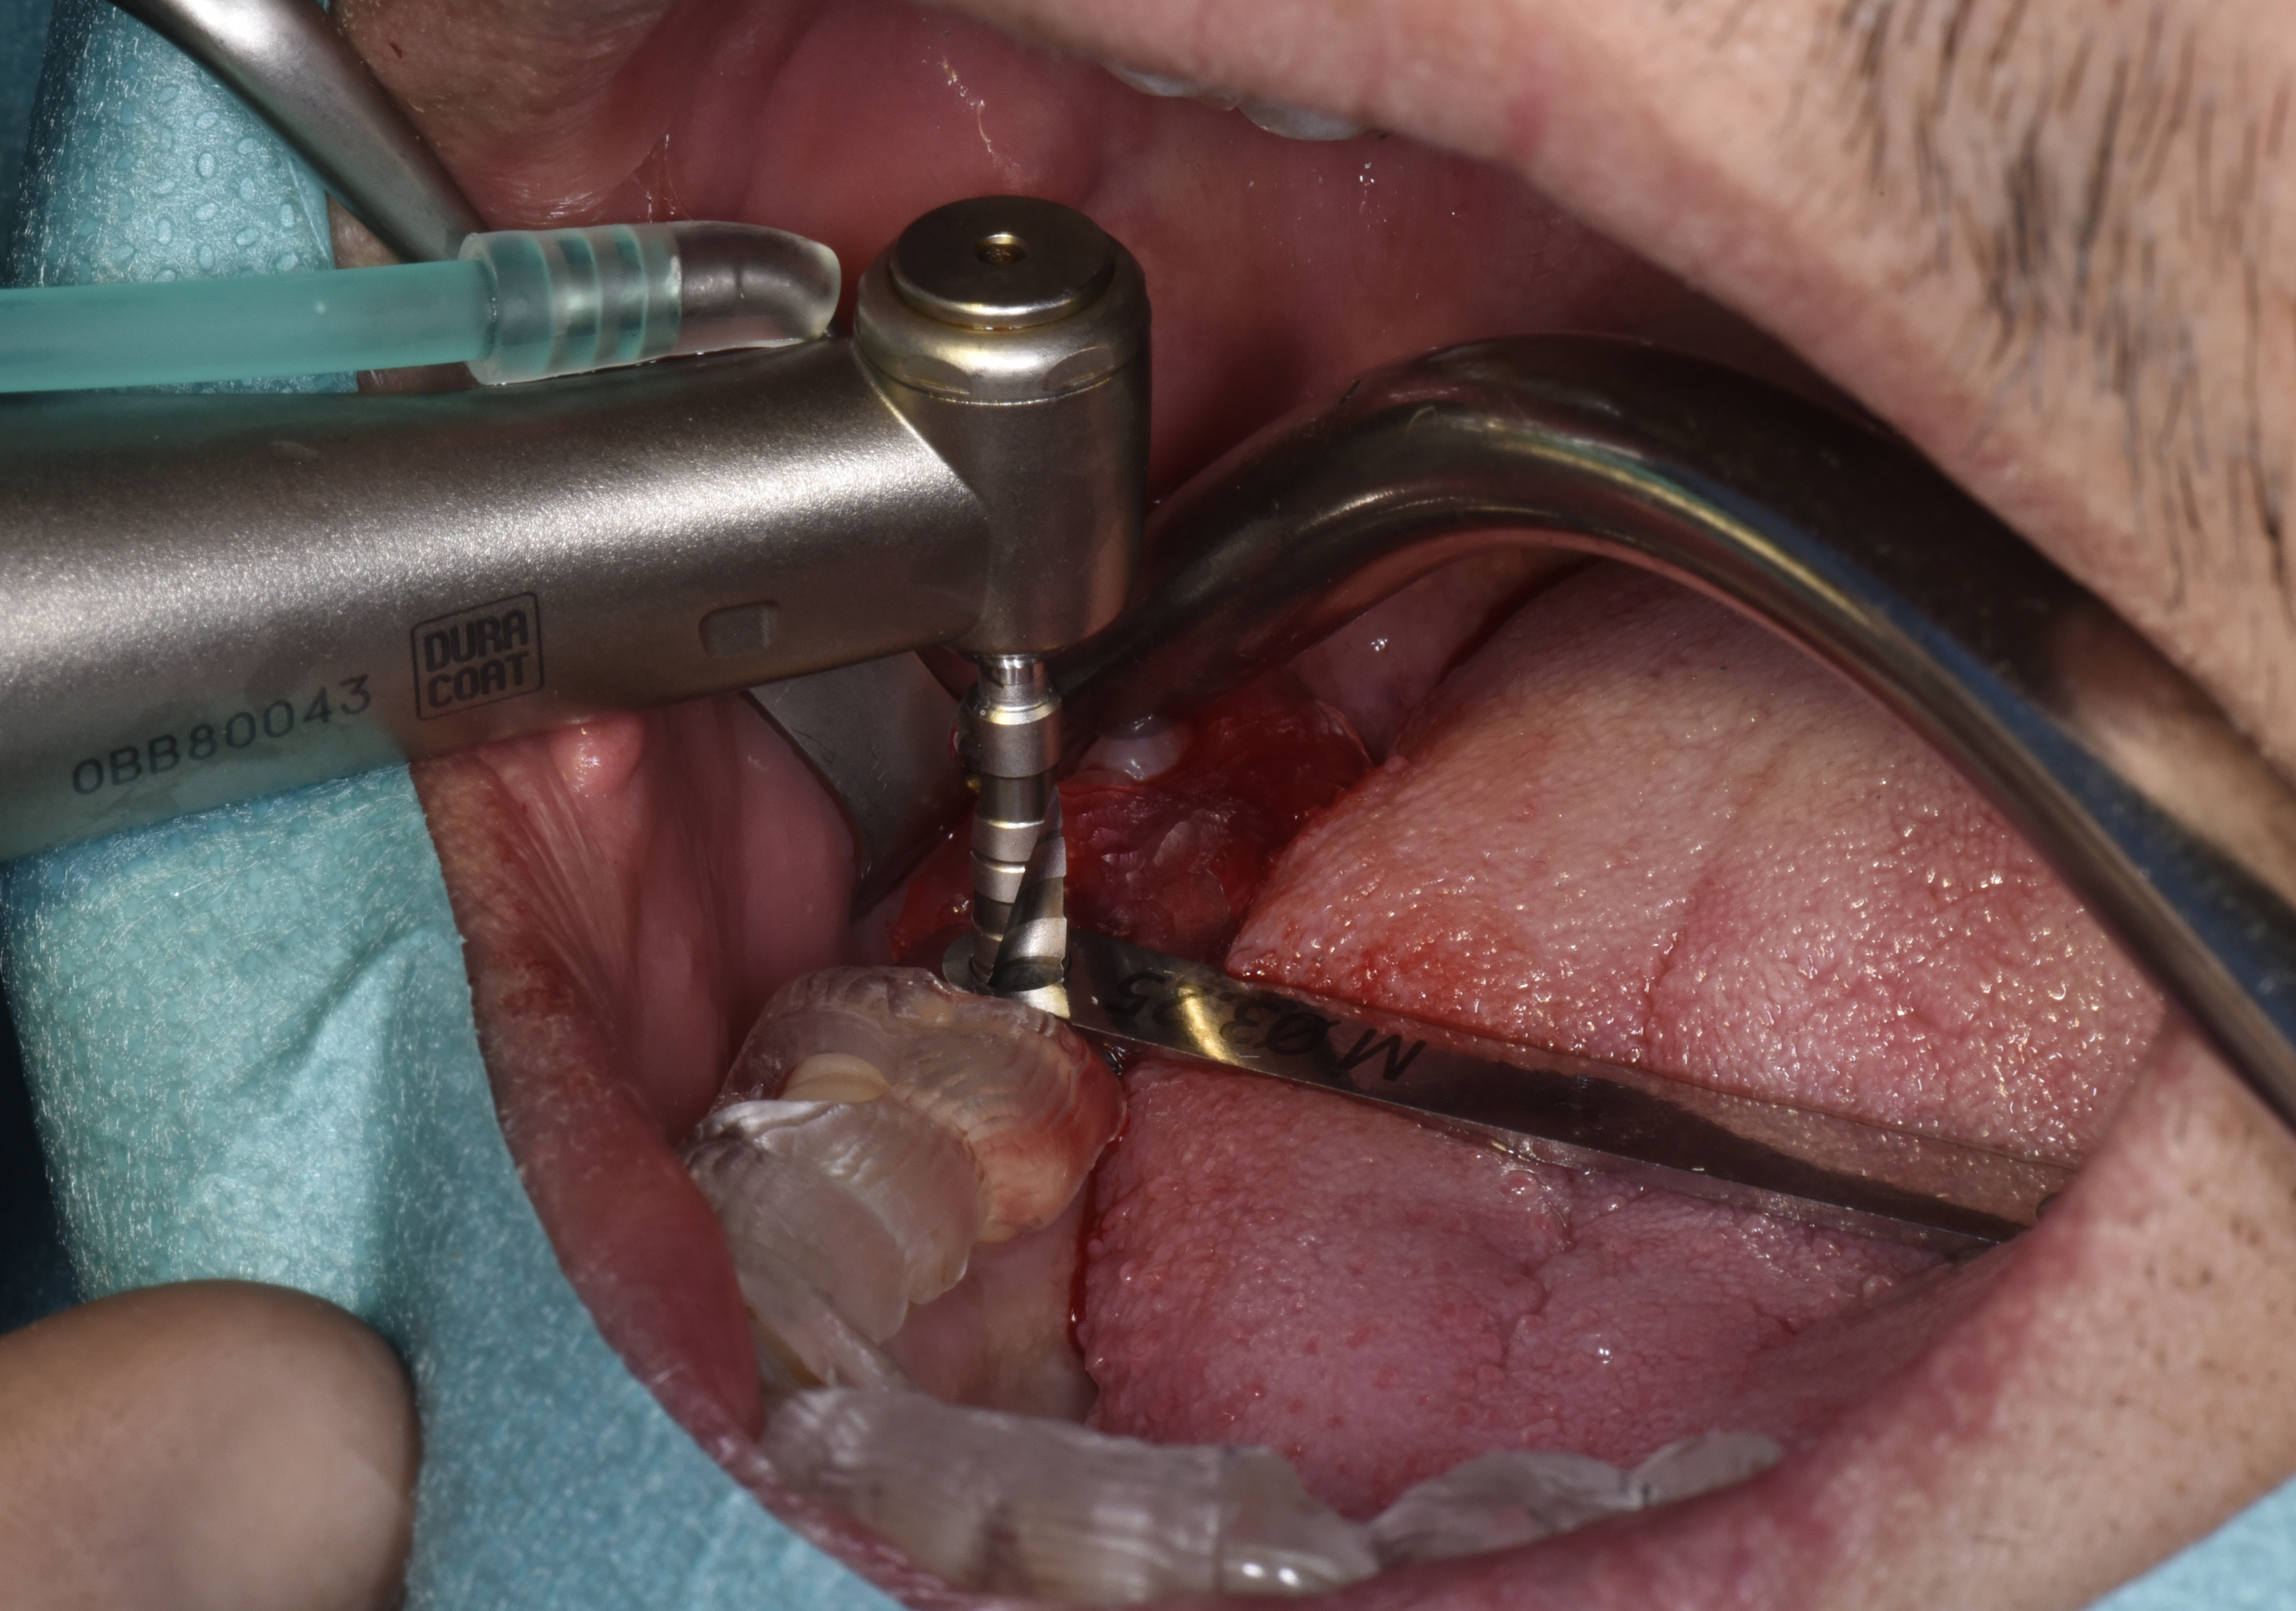

Le guide chirurgical est mis en place. Des douilles de guidage sont utilisées pour le passage des différents forets (Fig. 8). Elles présentent pour diamètre intérieur, le diamètre du foret à utiliser et pour diamètre extérieur le diamètre de l’orifice usiné dans le guide chirurgical. De cette façon l’axe de l’implant défini lors de la planification est parfaitement respecté. De plus, la position de l’extrémité supérieure de la douille étant également définie lors de la planification implantaire, la profondeur de forage est elle aussi parfaitement respectée, ce qui permet de préserver les structures anatomiques sensibles. La mise en place guidée de l’implant permettra de garantir la plus grande précision dans le positionnement final de ce dernier.